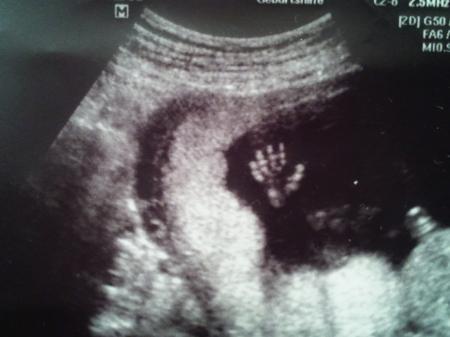

Mein kleiner wollte mal winken

Bild zu US Bild - Forum für April - Mamis